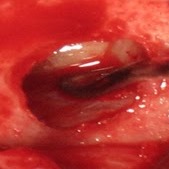

Μια άλλη περιοχή του στόματος που μπορεί να δέχεται μακροχρόνιο ερεθισμό είναι ο βλεννογόνος των φατνιακών αποφύσεων, δηλαδή τα νωδά ούλα που στηρίζουν τις ολικές οδοντοστοιχίες. Η αντιδραστική βλάβη που μπορεί έτσι να εκδηλωθεί ονομάζεται ινώδης πτυχωτή υπερπλασία (Εικόνα 8).

Εικόνα 8. α. Περίπτωση κάτω δεξιάς αντιδραστικής υπερπλασίας (βέλος) – στο ένθετο η βλάβη παρασκευασμένη πριν την αφαίρεση, β. Άλλη περίπτωση κάτω αριστερής αντιδραστικής υπερπλασίας.